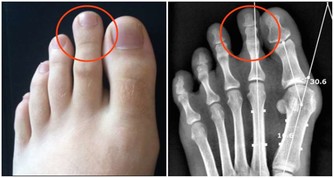

2、指甲易斷、可能氣血不足了

“肝,其華在爪”,意思是如果肝血充足的話,內在的光華就會表現在指甲上,也就是說,指甲是人體健康的外在表現,從指甲的表現能看出肝的好壞。

是不是發現自己指甲不像以前那麼硬了,好不容易才留長的指甲,正準備週末去美甲的,沒想到洗了兩件衣服就折了。

指甲壁上還總起皮皮,嫌不好看忍著痛把皮皮揪掉,十有八九還會流血……

倘若指甲很長時間都不長,顏色枯槁、不夠潤澤,表面看起來也有些蒼白,變薄變脆,很容易就能折斷……等等,這是指甲營養不良的表現,也說明你的肝臟有了問題。